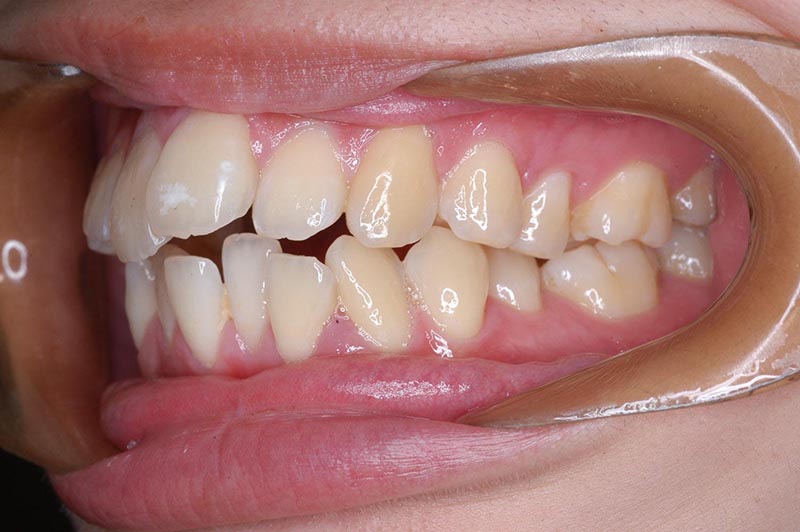

初診時

主訴 口が閉じづらい 診断名 アングルⅠ級上下顎前突症例

初診時年齢 19歳5ヵ月 性別 動的治療期間 26ヵ月

口腔内所見 大臼歯関係はⅠ級。顔面正中に対して上顎正中は一致しており、下顎正中は右側に偏位していた。上下顎前歯は大きく唇側傾斜し、overjetが7.8mmの上突咬合、両突歯列、叢生歯列弓であった。